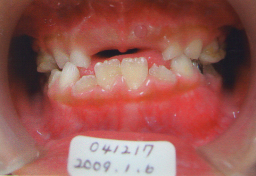

私の娘:掛園 綾です。2002年01月19日生 2007年03月19日(5才2ヶ月) 骨格性反対咬合(C〜C) 矯正用の床装置を作っても寝ると すぐ自然に吐き出す。また床装置を入れると 寝れないと主張。 |